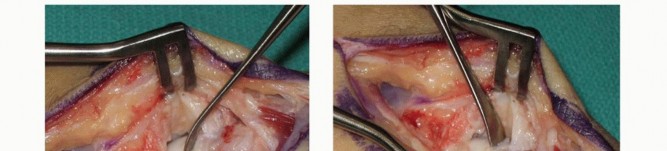

Rigid internal fixation is then achieved. A 0.035-inch guidewire for the cannulated headless compression screw is introduced from the distal scaphoid tubercle, directed proximally, dorsally, and ulnarly, aiming for the absolute central axis of the proximal pole. The trajectory is verified in multiple planes using intraoperative fluoroscopy. Achieving a central position in the proximal pole is statistically correlated with higher union rates and superior biomechanical pull-out strength.

Once the guidewire trajectory is confirmed, the length is measured. The outer cortex of the distal scaphoid is over-drilled to allow the screw head to countersink beneath the articular cartilage. The appropriate length headless compression screw is then advanced over the wire. As the variable pitch threads engage, the surgeon will visually and fluoroscopically observe robust compression of the distal fragment, the intercalated wedge graft, and the proximal fragment into a single, rigid construct.

The final step involves a rigorous fluoroscopic examination to ensure anatomical reduction, proper screw length without joint penetration, and solid compression. The joysticks and guidewire are removed. The volar capsule is meticulously repaired using 3-0 or 4-0 absorbable sutures to restore radiocarpal stability. The pronator quadratus is allowed to fall back over the radial donor site, and the FCR sheath and skin are closed in layers. A sterile dressing and a well-molded volar thumb spica splint are applied before the tourniquet is deflated.